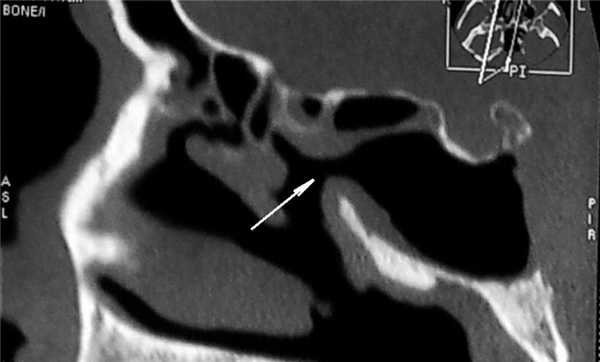

Послеоперационный период гладкий. На 5-й день произведен туалет оперированной полости под эндоскопическим контролем. Для лучшего осмотра оперированной полости также использована модель ULYSS. На 7-й день после операции отведение левого глаза восстановилось на 80%, исчезла головная боль. При эндоскопическом исследовании соустье клиновидной пазухи слева широкое, функционирует, что подтверждено данными КТ (рис. 3). Рисунок 3. Компьютерная томограмма ОНП (аксиальная проекция) больного Е. на 7-е сутки после операции по поводу грибкового тела. Воздушность клиновидной пазухи полностью восстановлена, естественное соустье пазухи достаточного размера (указано стрелкой), что обеспечивает адекватную аэрацию пазухи в послеоперационном периоде. Однако в связи с частичным разрушением канала левой внутренней сонной артерии пациенту рекомендовано динамическое наблюдение.